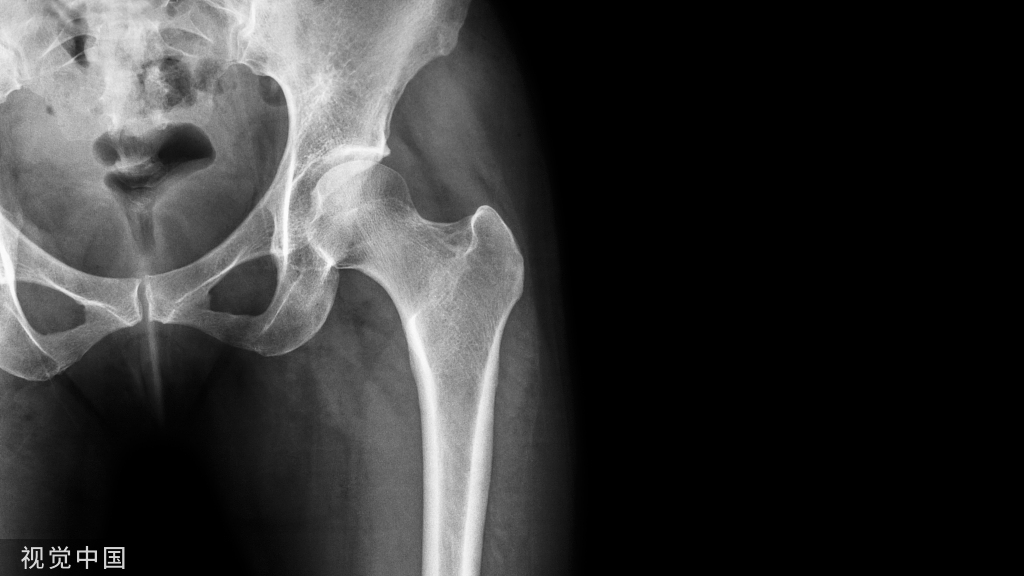

上图左侧为患侧肢体,中间为临摹的健侧骨骼轮廓。右侧图将临摹后的纸张翻转后贴于C臂机显示屏,作为术中复位模板。术后亦可利用该模板对固定后的骨折进行比对。